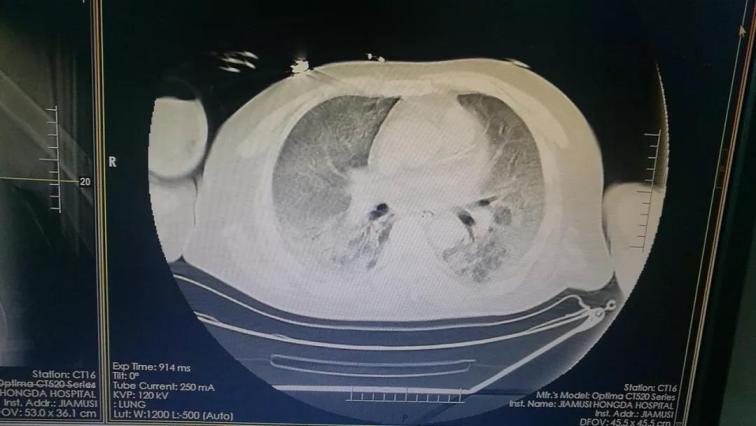

5月15日佳木斯大學(xué)宏大醫(yī)院重癥醫(yī)學(xué)科(ICU)收治1例急性上呼吸道重癥感染的患者。該患者繼往有腎病綜合征病史,在鶴崗市三甲醫(yī)院診斷為頑固性ARDS。CT片顯示雙肺透過度減低,并見大片高密度影,部分病灶實(shí)變,其中可見支氣管氣相,俗稱“大白肺”。當(dāng)?shù)蒯t(yī)院認(rèn)為此患者已經(jīng)沒有搶救價(jià)值了。